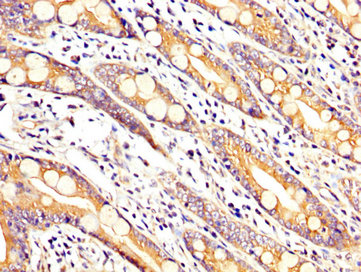

IHC image of CSB-PA850791LA01HU diluted at 1:200 and staining in paraffin-embedded human small intestine tissue performed on a Leica BondTM system. After dewaxing and hydration, antigen retrieval was mediated by high pressure in a citrate buffer (pH 6.0). Section was blocked with 10% normal goat serum 30min at RT. Then primary antibody (1% BSA) was incubated at 4°C overnight. The primary is detected by a biotinylated secondary antibody and visualized using an HRP conjugated SP system.